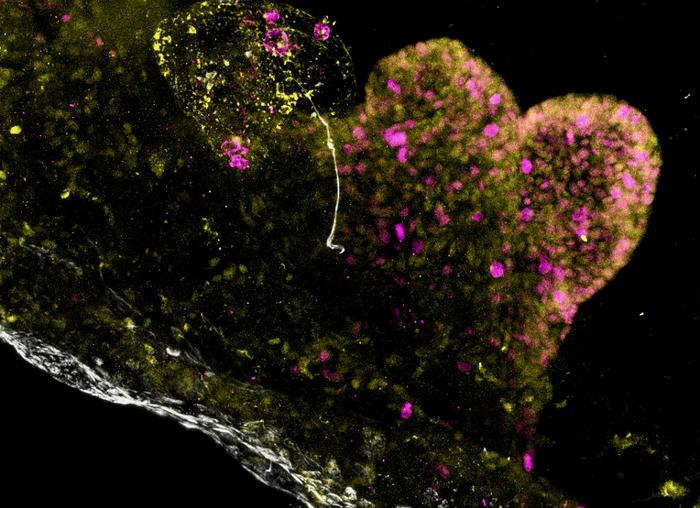

Immunofluorescence image of the antral side of a multi-regional assembloid derived from PMM2 patients, showing overgrowth of cells in the lumen of the assembloid. Cell replication marker KI67 in magenta, PDX1 in yellow, mucin in white.

B. Jones, G. Benedetti et al., Nature Biomedical Engineering